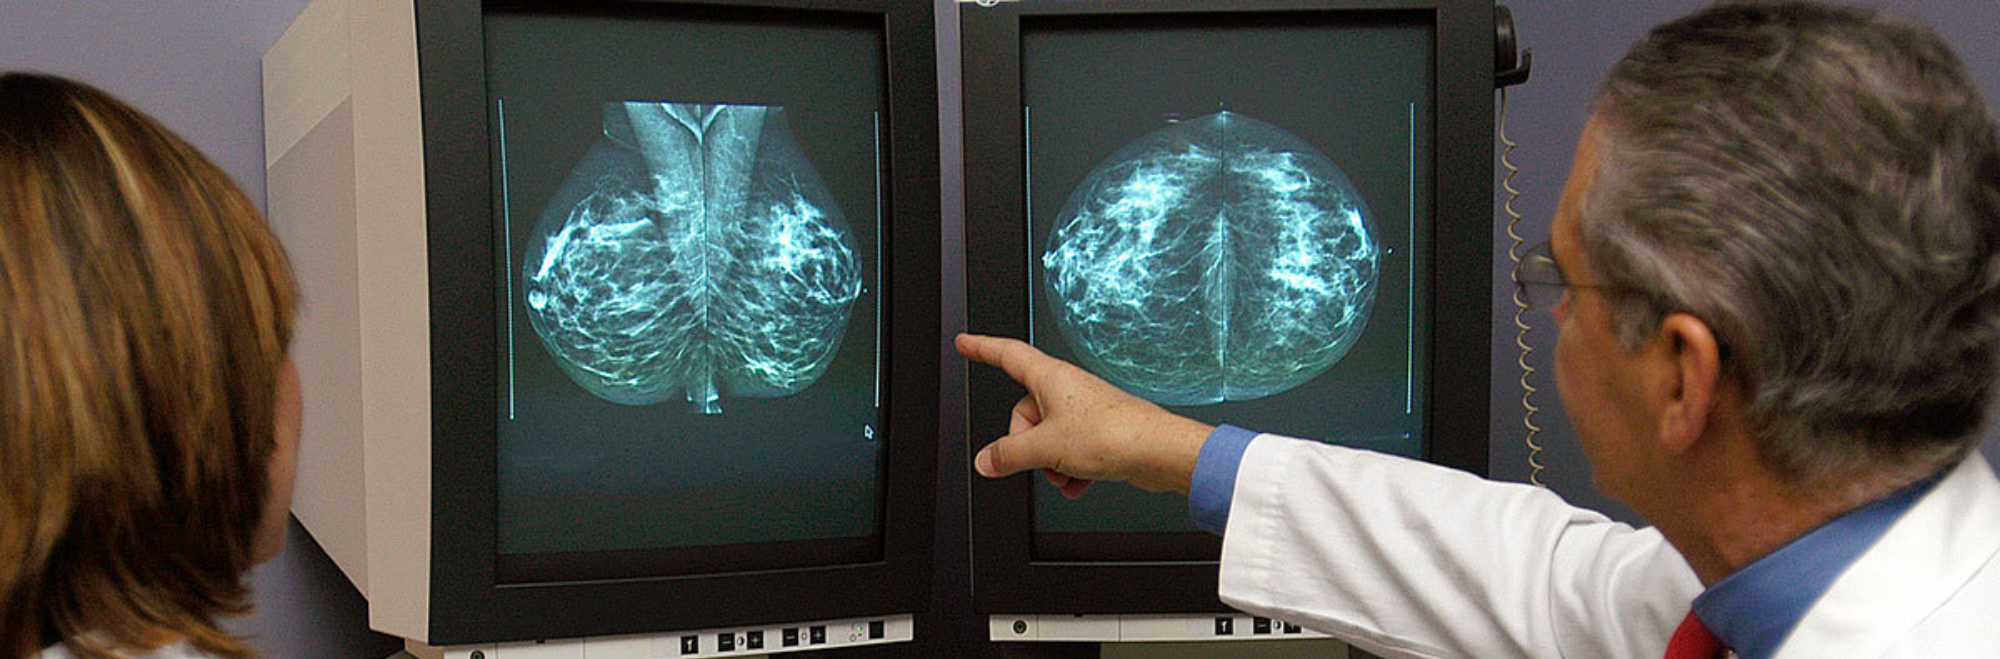

A radiology test that takes X-ray images of the breast used to look for abnormalities including masses or abnormal patterns of microcalcifications.

An imaging technique that uses beams of radiation (X-rays) to take an image of the body. A mammogram is a specialized form of an X-ray image.

A term used to describe a test used to look for a disease before it has caused symptoms. Mammograms are the primary screening test used to look for breast cancer in women.